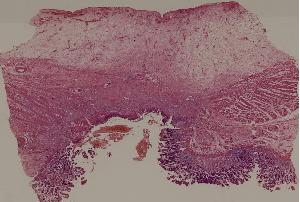

59.慢性萎缩性胃炎

60.胃溃疡

61.胃腺癌(胃粘液腺癌)